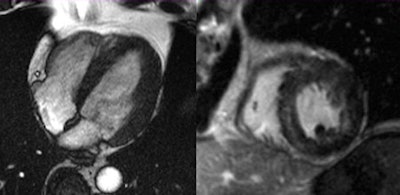

The major benefit of MRI is that it visualizes both the anatomy and the function of the heart in detail, and this makes it possible to detect conditions of the muscle as well as impaired wall motion and issues regarding oxygen supply or the pumping function. Emrich's team used cardiac MRI to examine 125 patients presenting with chest pain, elevated levels of troponin, and uncertain catheterization results. A diagnosis was established based on results from the MRI examination. A diagnosis based on the consensus of experts, including radiologists and integrating the subsequent clinical progression, served as a reference.

For 90% of these cases, cardiac MRI yielded the correct result, as was shown by a comparison with the reference diagnosis. Conditions associated with chest pain and elevated troponin levels include myocarditis, dilatative cardiomyopathy, Takotsubo cardiomyopathy, and hypertensive heart disease. In some cases, a myocardial infarction was shown that had not been detected by catheterization.